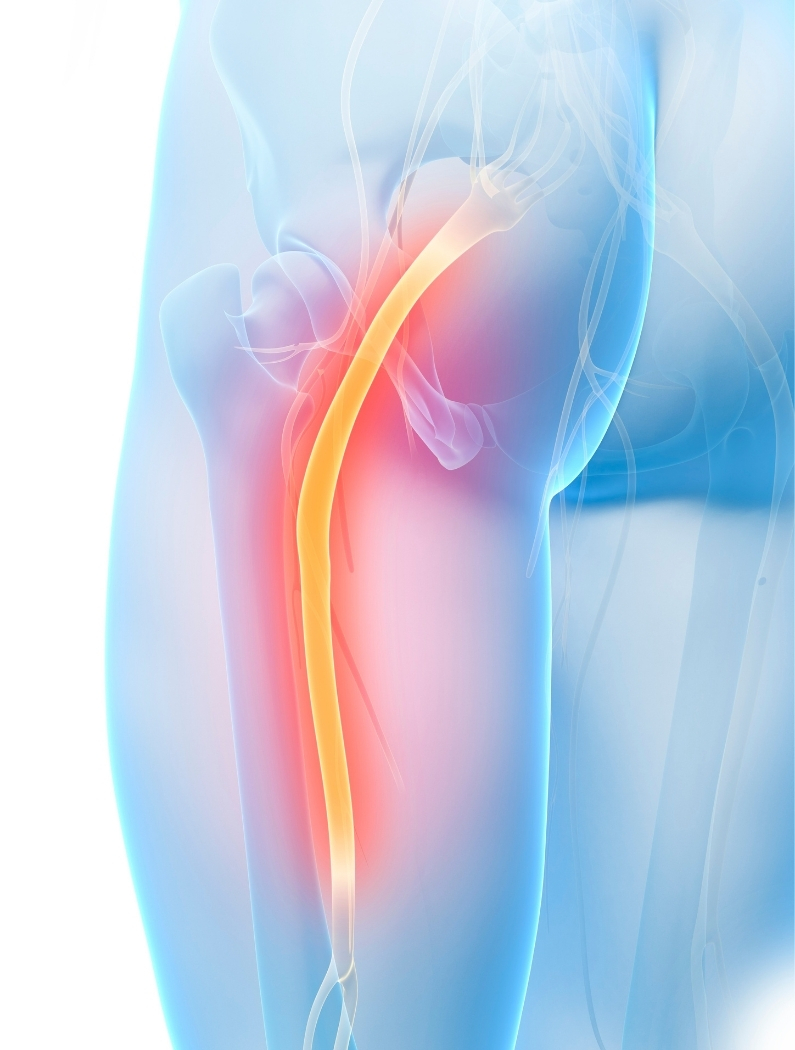

La ciática se refiere a un conjunto de síntomas asociados a la irritación o compromiso del nervio ciático,

el nervio más largo del cuerpo. Generalmente se manifiesta como una molestia que inicia en la zona baja

de la espalda o glúteo y puede irradiarse hacia la pierna.

La ciática no es un diagnóstico en sí mismo, sino una manifestación de que algo está influyendo

en el trayecto del nervio ciático. Este nervio se origina en la región lumbar y sacra y

recorre glúteos, muslo y pierna.